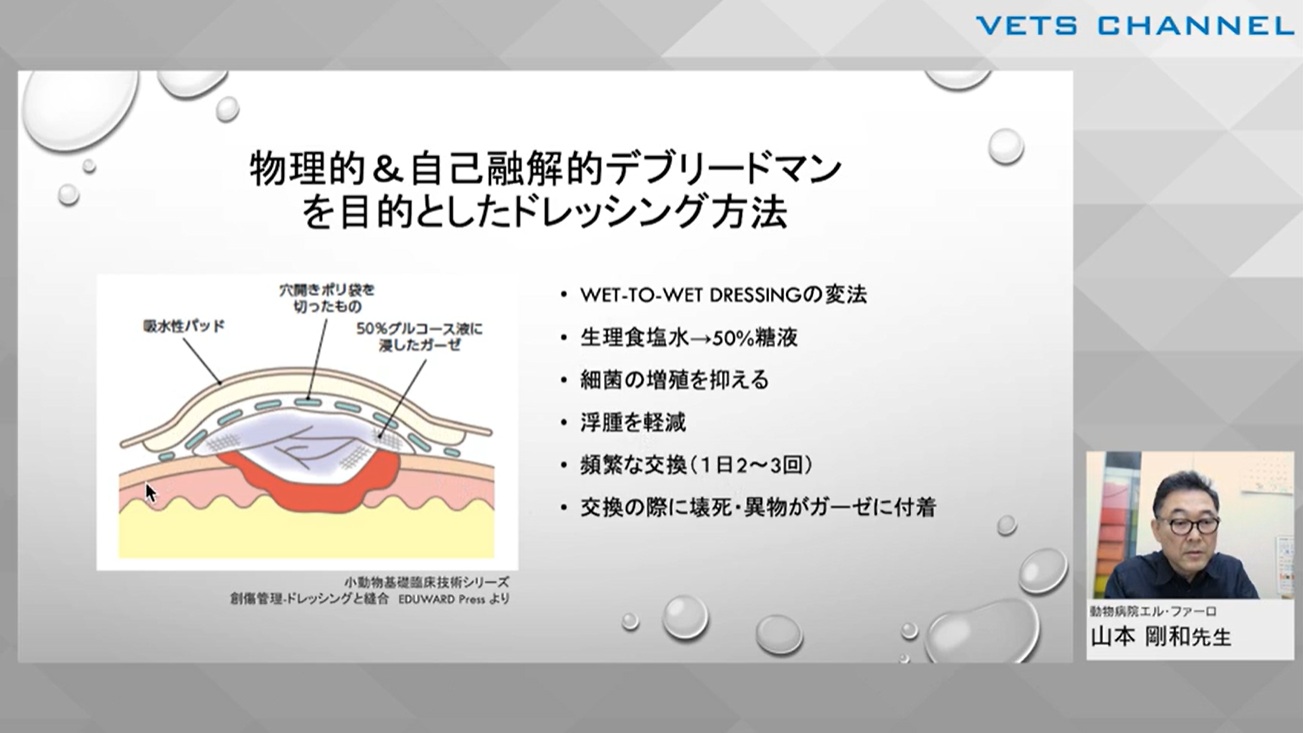

ビジュアルで網羅する 創傷管理

- セミナー

- 内科全般

- 軟部外科

- 皮膚科

- 犬

- 猫

- エキゾ

山本 剛和先生 (動物病院エル・ファーロ)

96分

2025/09/26